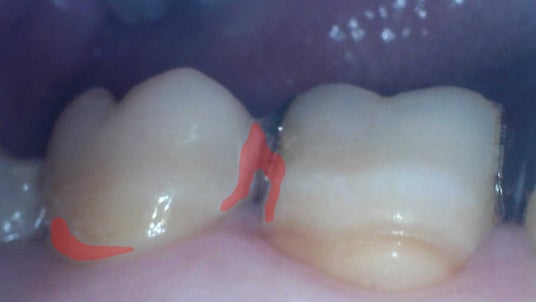

画像認識AIが認識した汚れ付着部位を赤く示した画像

「口腔ケアサポート技術」では、専用口腔内カメラを使用して自身で撮影した口腔内画像を画像認識AIサーバーへ送信すると、画像認識AIが汚れ付着箇所を認識し着色を行います。

検査対象画像

発見した汚れ部位を赤く示した画像

なお本活動では、口腔内画像を1000枚以上収集して画像認識AIを構築し、本AIによる汚れ発見の精度はIoU0.421(※3)です。